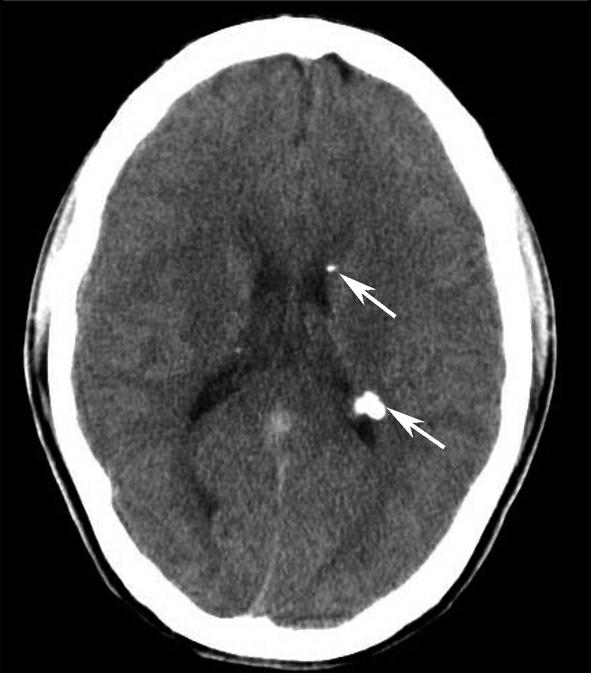

图1-2-4 右侧颈静脉球瘤

A.横断面(骨窗);B.横断面

右侧颈静脉孔区不规则骨质破坏(箭),局部见软组织肿块(☆)